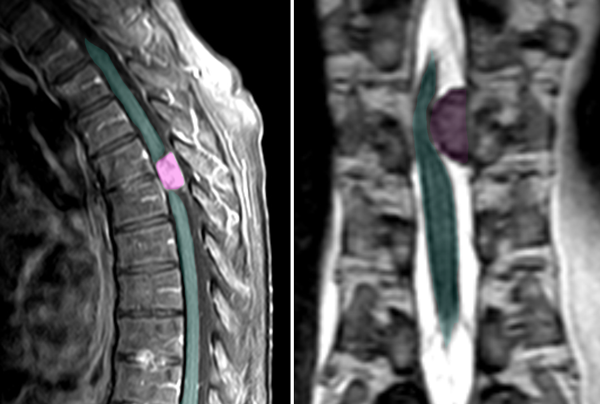

Mηνιγγίωμα θωρακικής μοίρας της σπονδυλικής στήλης με σημαντική πίεση στον νωτιαίο μυελό. |